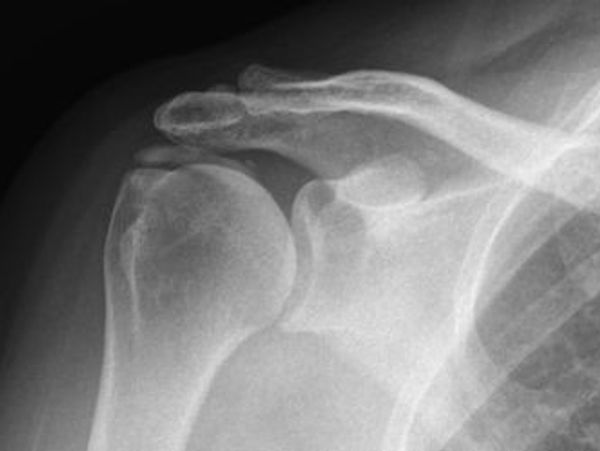

Day 1 will start with a review of calcific tendinopathy (simple to challenging cases), how to treat for best outcomes and multidisciplinary care. This will lead into a deeper look at shoulder disorders on imaging including plain film, US, CT and MRI.

TOPIC 11 - CALCIFIC TENDINOPATHY

TOPIC 12 - UNDERSTANDING IMAGING - PEARLS & PITFALLS

A patient is referred to you for severe right shoulder pain of 2 weeks. She complains of regular night pain, difficulty with arm movement and no prior history of shoulder disorders. No trauma, minimal improvement with physiotherapy in her community, a recent flare with massage and no effect of regular OTC NSAID use. Right dominant.

Examination reveals difficulty in early movement, particularly flexion and abduction (limited to 30 deg). Muscle power around the shoulder is reduced 4-/5 in elbow flexion, abduction, IR and ER, limited by pain. Special tests are limited. No muscle loss around the scapula. She is tender to palpation over the ACJ and subacromially. Passive movement in ER is moderately restricted (50.70,90 throughout standard abduction points), with GHJ abd to 80 deg.